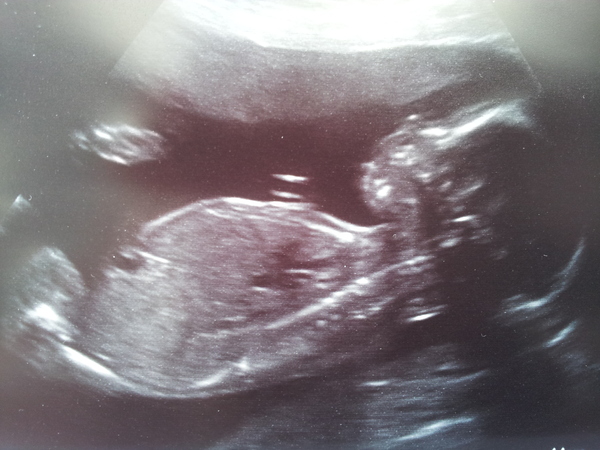

Had a 4d scan yesterday it was really incredible he looks like a proper little baby!! GrinGrin

Thread #8 - TTC#1 Grads - stripy bump photos ahoy!